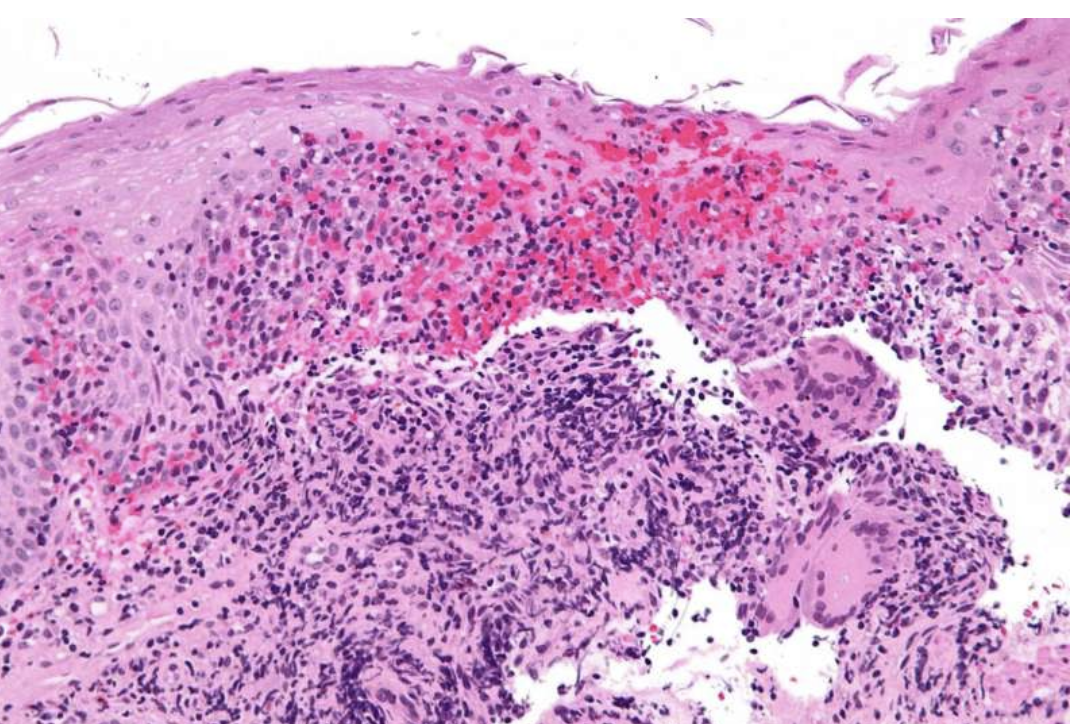

哎呀,说起克罗恩病,真是让人头疼。这种慢性肠道炎症,时不时的就会让人痛不欲生。但是,听说有一种叫类克的治疗方法,好像挺神奇的。我今天就以一个曾经饱受克罗恩病折磨的患者的身份,跟大家聊聊这个类克治疗到底靠不靠谱。

首先得说,类克这玩意儿,不是那种一吃就灵的灵丹妙药,它的效果得看个人。我用了以后,感觉像是在黑暗中看到了一线光明。刚开始用的时候,真是期待又紧张,生怕没效果,白白浪费时间和金钱。但是,慢慢的,我发现自己的症状有所缓解,不再像以前那样频繁地腹泻,腹痛的次数也减少了。

当然,这种治疗也不是没有副作用。我有时候会感到疲倦,偶尔也会有头痛,但跟之前的痛苦相比,这些都是小儿科了。而且,医生也说,不是每个人都能适应类克,有的人可能效果就不明显。

总的来说,对我而言,类克就像是一盏明灯,照亮了我前行的路。